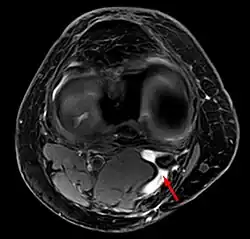

In adults, Baker's cysts usually arise from almost any form of knee arthritis (e.g., rheumatoid arthritis) or cartilage (particularly a meniscus) tear. Baker's cysts in children do not point to underlying joint disease. Baker's cysts arise between the tendons of the medial head of the gastrocnemius and the semimembranosus muscles. They are posterior to the medial femoral condyle.

Diagnosis is by examination. A Baker's cyst is easier to see from behind with the patient standing with knees fully extended. It is most easily palpated (felt) with the knee partially flexed. Diagnosis is confirmed by ultrasonography, although if needed and there is no suspicion of a popliteal artery aneurysm then aspiration of synovial fluid from the cyst may be undertaken with care. An MRI image can reveal presence of a Baker's cyst.